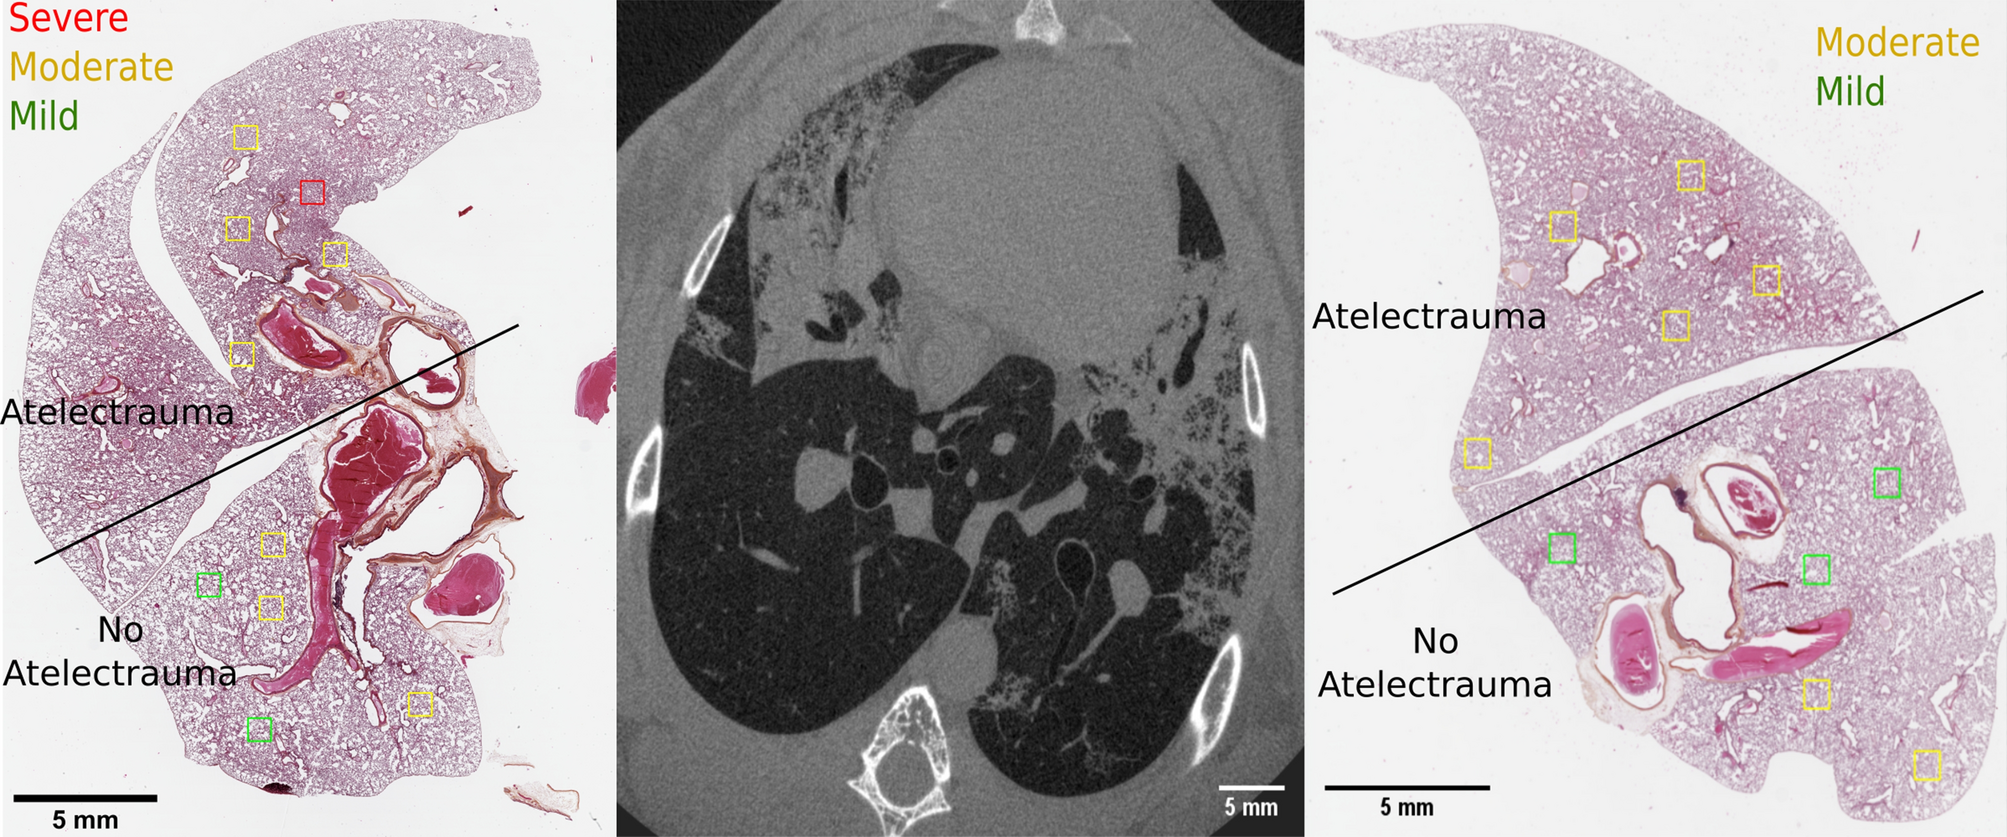

Figure 7

From: Imaging atelectrauma in Ventilator-Induced Lung Injury using 4D X-ray microscopy

HES staining of the lung tissue and corresponding in vivo dynamic 3D microscopy for Rabbit 3. On the HES images, the regions of interest chosen for the qualitative evaluation are shown, using a color coding representing the score given by the pathologist. The regions of interest were chosen in areas showing R/D in the CT and in areas not showing it, in order to compare the spatial distribution of R/D and injury.